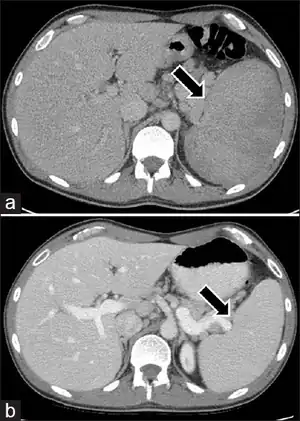

Medical imaging

Radiologic imaging will demonstrate enlarged lymph nodes in multiple regions, which are typically 18F-fluorodoxyglucose (FDG) avid on positron-emission tomography (PET).[9]